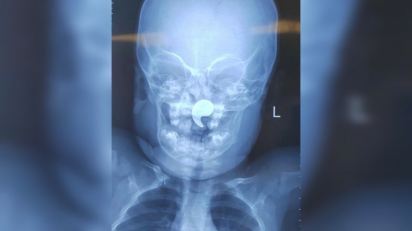

Врачи спасли полуторагодовалую девочку — в носу застрял…

Полуторагодовалая девочка едва не задохнулась из‑за магнита в форме запятой, который попал ей в носоглотку во время игры. Благодаря оперативным действиям врачей детской больницы № 1 ребёнка удалось спасти, сообщили в минздраве Воронежской…